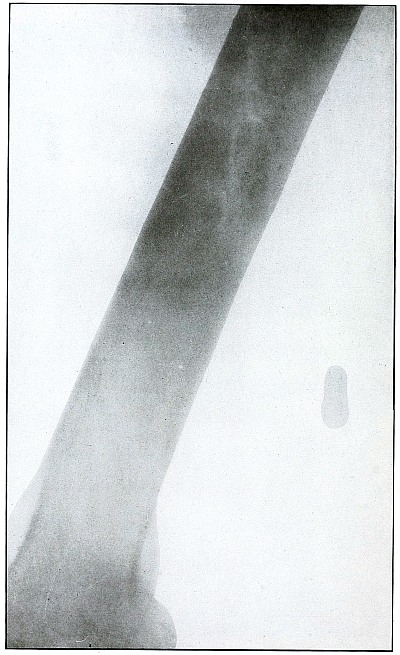

Gunshot fracture, tibia and fibula |

130 |

| 61. |

Gunshot fracture, tibia and fibula |